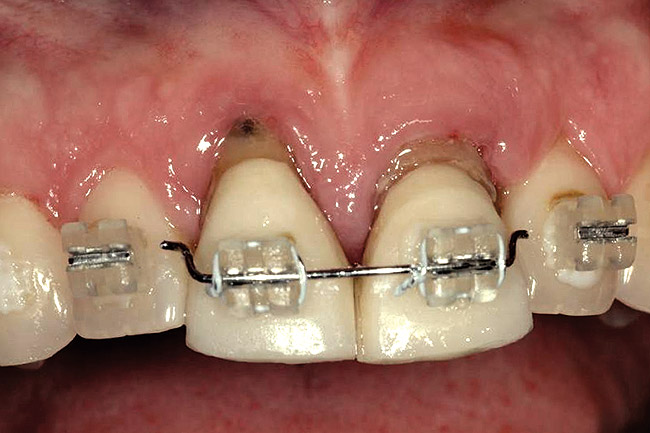

Figure 5  A patient presented needing both centrals extracted. Note the excellent papillary height and free gingival margin location.

Figure 5

Figure 6  Excellent interproximal crestal bone level between the centrals before extraction.

Figure 6

Figure 7  Because the interproximal crestal bone was maintained and the soft tissue supported at the time of tooth removal, an excellent interimplant papilla exists.

Figure 7

Figure 8  Maintenance of interproximal crestal bone following final restoration placement.

Figure 8

Figure 9  The final restorations exhibit a minimal 1-mm to 1.5-mm change in papilla height when compared with the pre-extraction height.

Figure 9